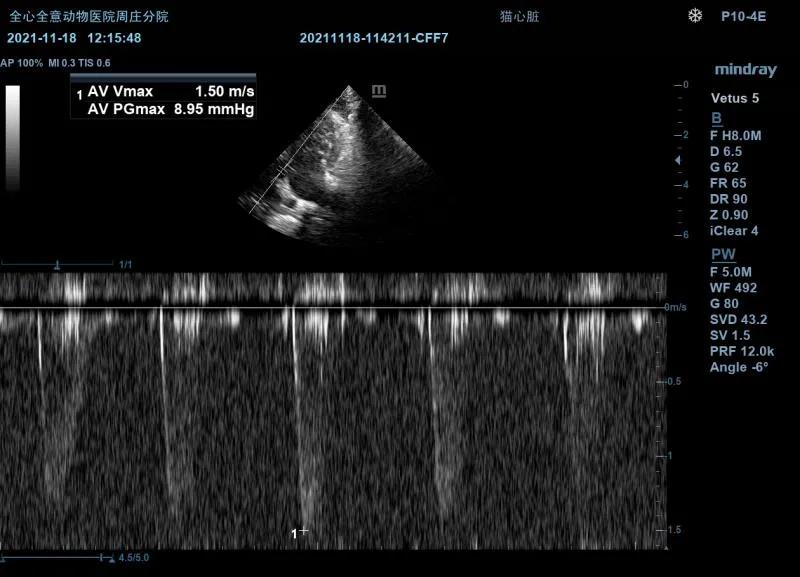

超声检查:

左侧测量瓣膜口流速正常。